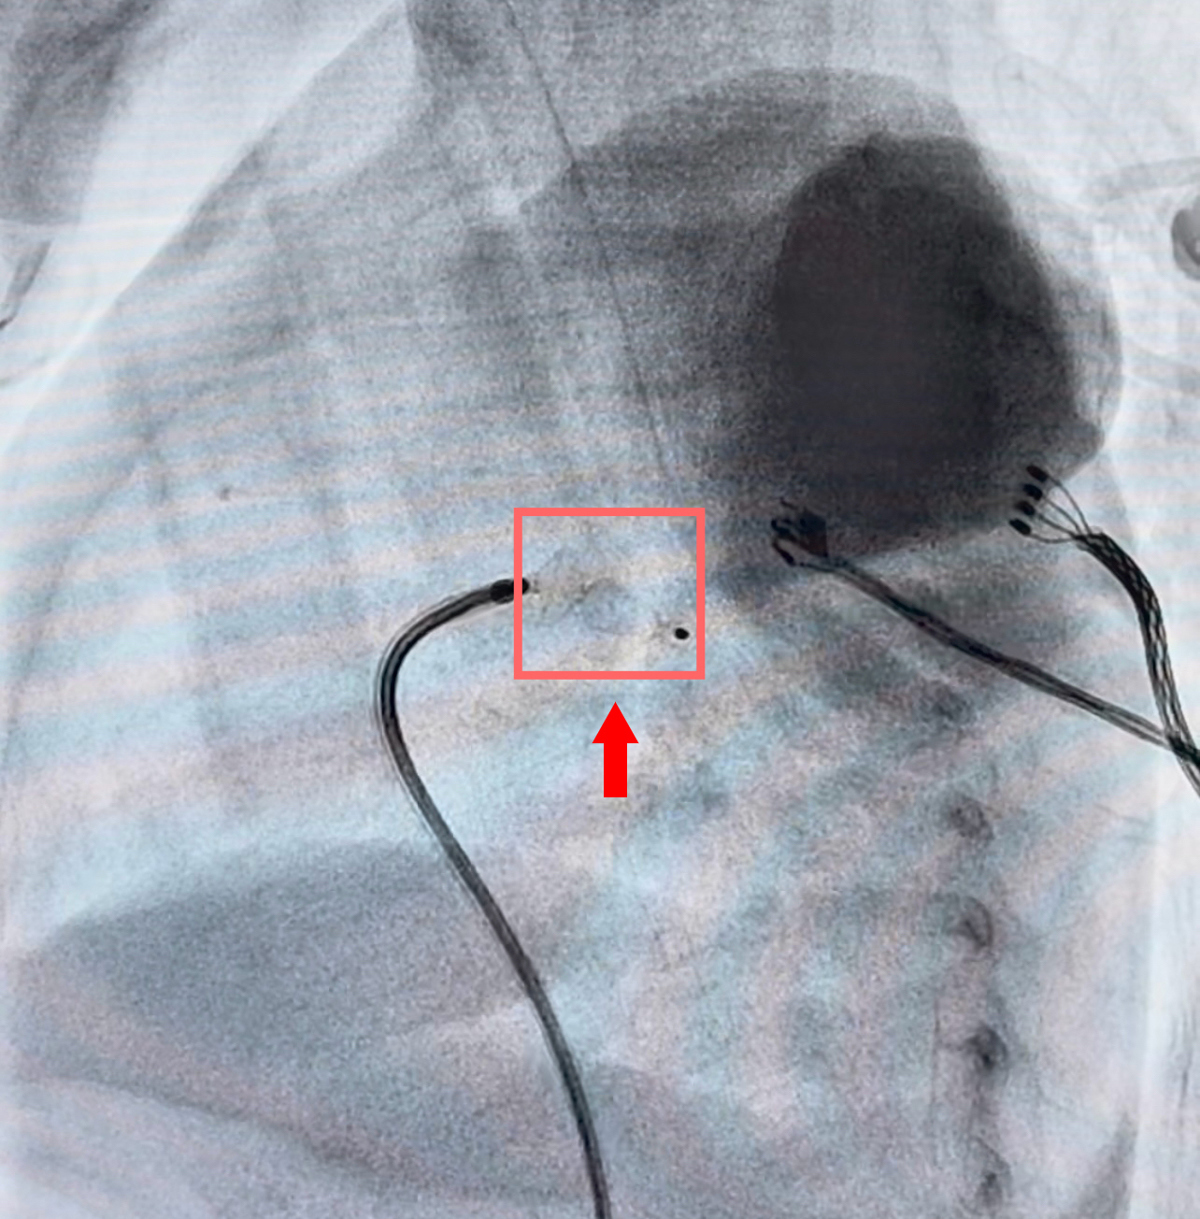

4月8日上午,在全身麻醉及全程超声引导下,介入团队通过穿刺股静脉建立通道。在X光与超声的双重“导航”下,李恒主任凭借精湛技术,小心翼翼地将导丝和输送鞘穿过比头发丝粗不了多少的血管,精准定位到未闭合的动脉导管处。随着封堵器的完美释放,造影显示:动脉导管分流瞬间消失!

整台手术操作时间仅约40分钟,出血量极少。术后即刻超声显示:封堵器位置稳定,无残余分流,心脏杂音消失。“手术成功了!”术后,橙橙的心功能明显改善,呼吸机参数顺利下调,生命体征平稳。